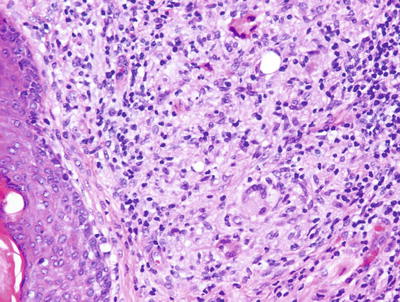

Acne rosacea demonstrates a perifollicular lymphohistiocytic infiltrate with spongiosis at the level of the infundibulum (Fig. 10.13). Sebaceous hyperplasia is present in many cases. Florid cases may have a granulomatous inflammatory response to ruptured follicular epithelium (Figs. 10.14 and 10.15).

Fig. 10.13

Granulomas with multinucleated giant cells located in the region of pilosebaceous units are characteristic of acne rosacea

Fig. 10.14

A caseating granuloma is present in acne rosacea

Fig. 10.15

Granulomas adjacent to follicular units are a diagnostic feature of acne rosacea